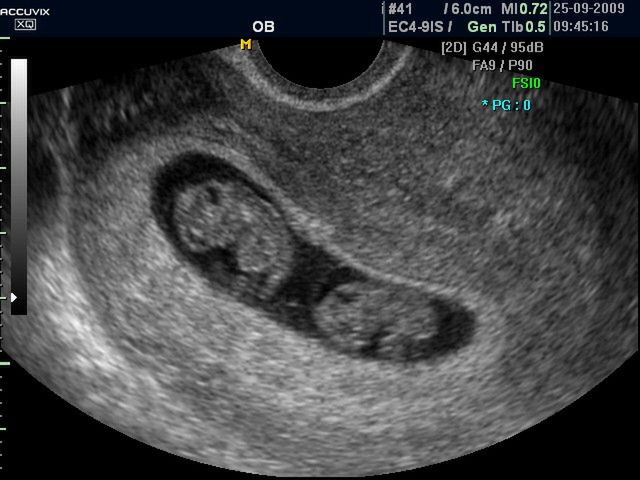

Płód w 9 tygodniu ciąży (bliźniaki jednokosmówkowe) -zdjęcia

W 9 tygodniu kształtują się nos, usta, powieki. Zanika charakterystyczny dla embriona ogonek